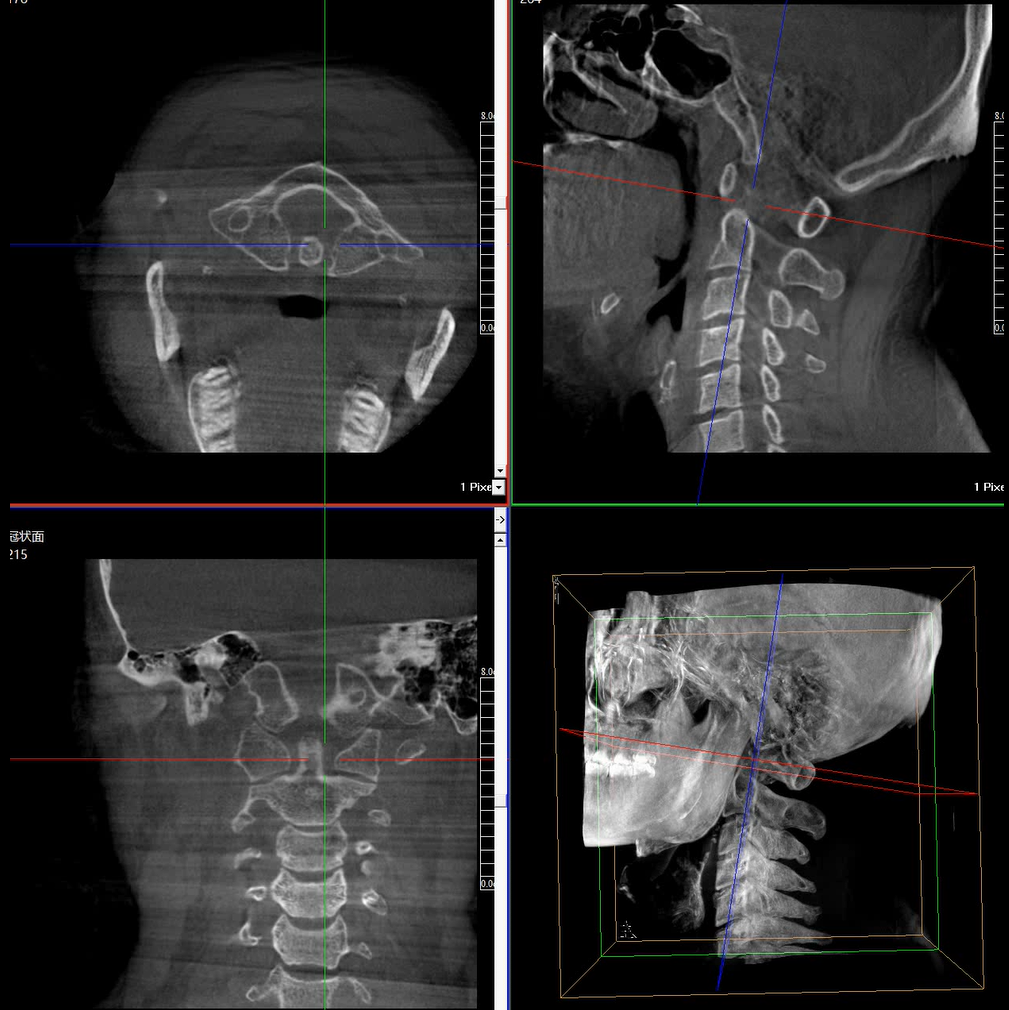

術(shù)中三維成像和橫斷面圖像提供多角度的手術(shù)診斷信息,輔助醫(yī)生進行術(shù)中評估判斷,諸如骨折復位情況和內(nèi)植入螺釘?shù)某叽绾臀恢茫o助手術(shù)更好地完成。

提供更大的術(shù)中三維成像視野,采集更多圖像信息,可一次拍全全段頸椎、全段腰椎、七節(jié)胸椎、雙側(cè)骶髂關(guān)節(jié)、股骨頭及單側(cè)盆骨。